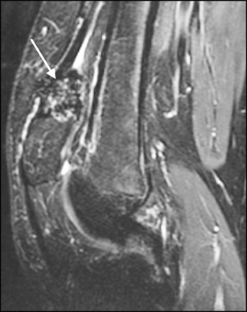

Synovium is the thin membranous lining of a joint. It produces synovial fluid, which lubricates and nourishes the cartilage and bone in the joint capsule. Synovial diseases in children can be classified as normal structures as potential sources of pathology (synovial folds: plicae, infrapatellar fat pad clefts), noninfectious synovial proliferation (juvenile idiopathic arthritis, hemophilic arthropathy, lipoma arborescens, synovial osteochondromatosis, pigmented villonodular synovitis, reactive synovitis), infectious synovial proliferation (pyogenic arthritis, tuberculous arthritis), deposition disease (gouty arthropathy), vascular malformation, malignancy (metastasis) and intra-/periarticular cysts and cyst-like structures. Other intra-articular neoplasms, such as intra-articular synovial sarcoma, can mimic synovial disease in children.

Fig. 1